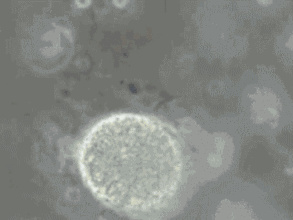

精子DNA的完整性,与精子功能有显著相关性,并且可以影响受精卵的分裂以及胚胎的发育。DNA位于精子的细胞核内,是遗传信息的载体,位置类似鸡蛋的蛋黄。精子DNA 损伤后,虽然看上去是“好”的,但其功能变差了,尽管不影响卵子受精,但容易导致胚胎发育不良和流产。精子DNA损伤严重的患者,即使可使卵子正常受精、分裂,但最后仍然可以导致流产。